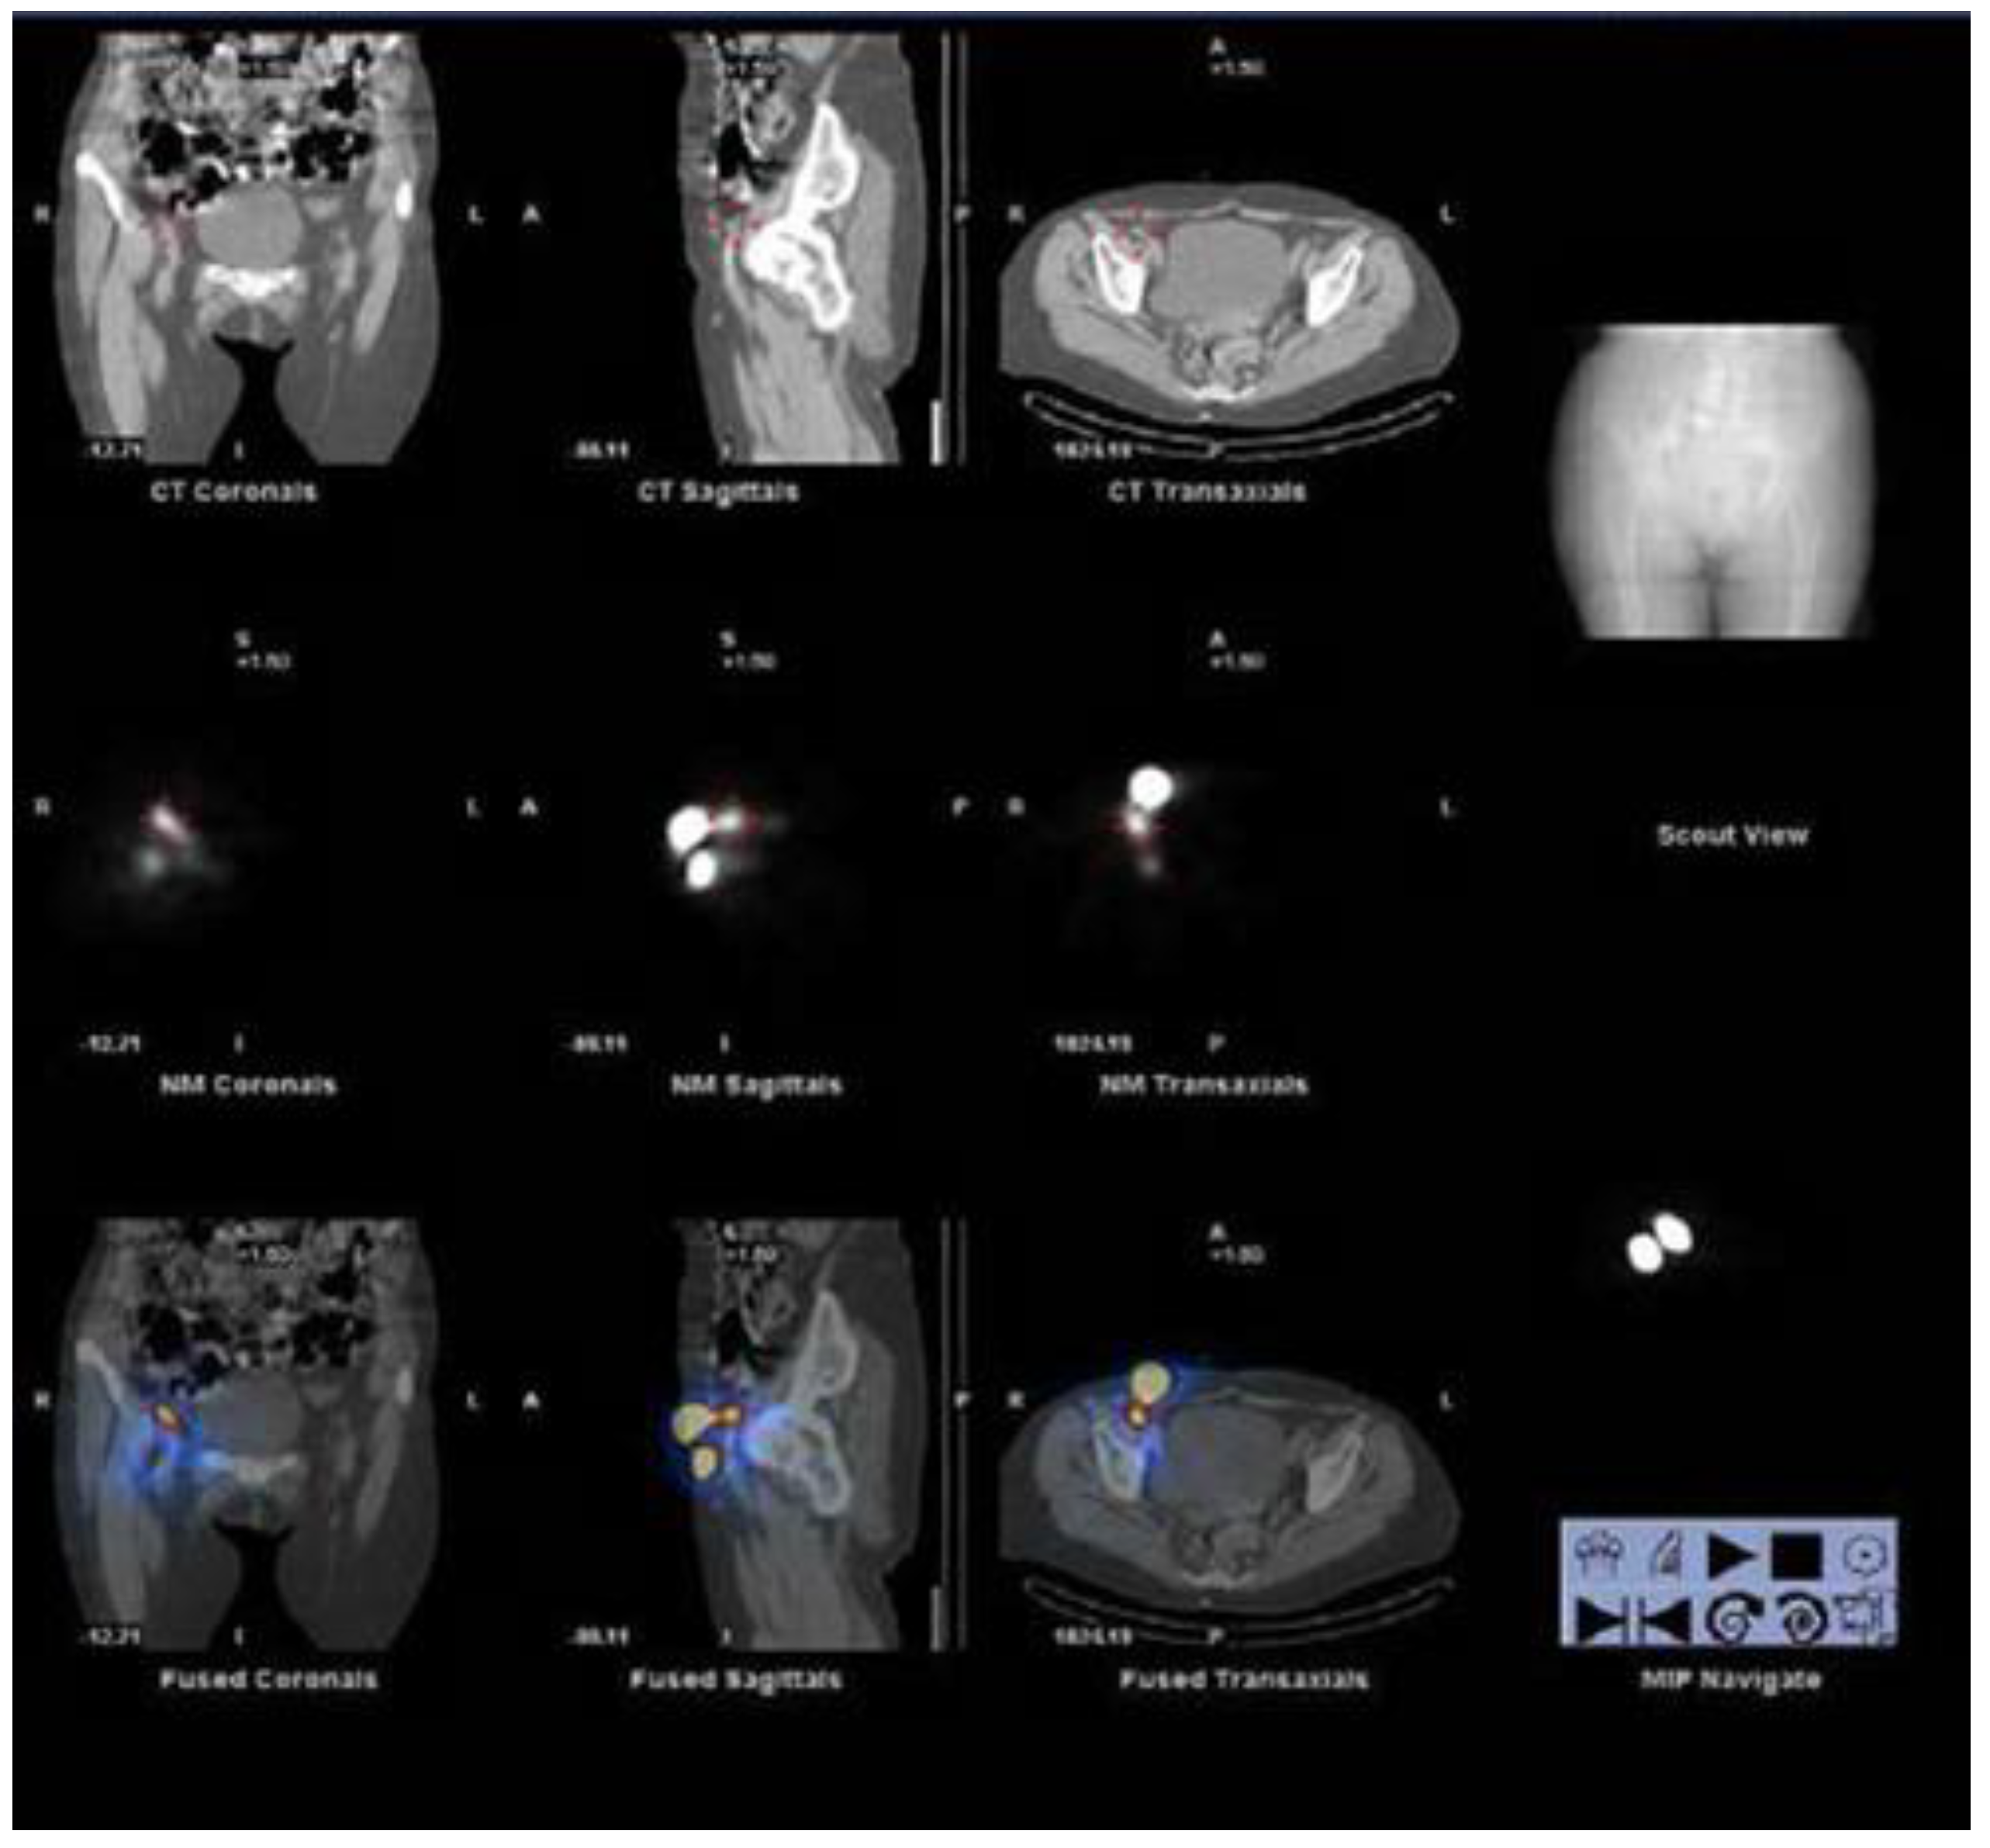

2. Lymphoscintigraphy